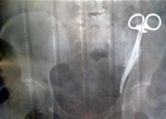

• A Woman Had Surgical Clamp Lodged In Her Abdomen For 23 Years!

A Woman Had Surgical Clamp Lodged In Her Abdomen For 23 Years!